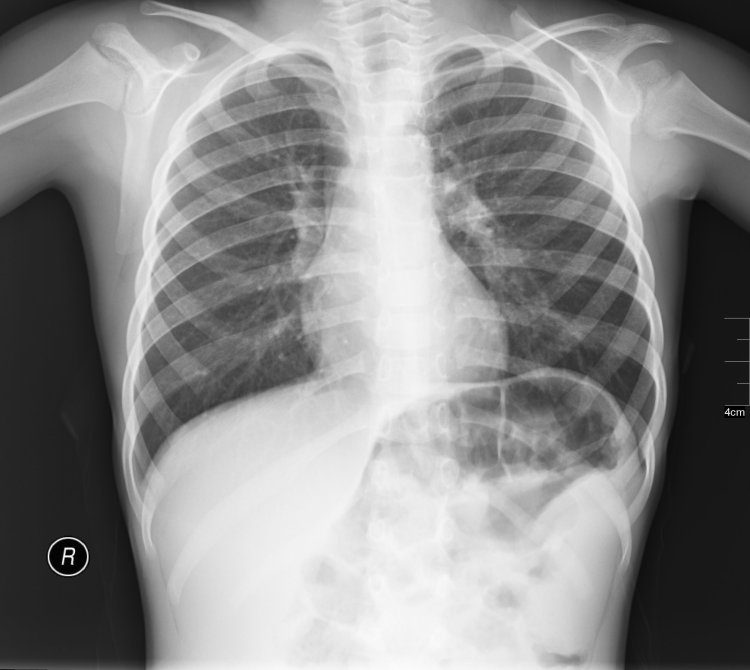

File:Radiology ND 0127 ADU.jpg - Wikimedia CommonsLa cintigrafía es una técnica no invasiva, lo que significa que no requiere incisiones ni procedimientos invasivos. El paciente simplemente recibe una inyección o una ingestión de una pequeña cantidad de radioisótopo. A continuación, se coloca en una máquina especial llamada gammacámara, que detecta la radiación emitida por el radioisótopo y la convierte en una imagen.